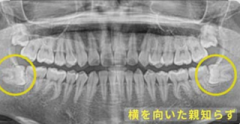

抜いた後 埋まります